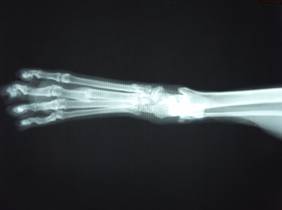

約2カ月後の様子。

足の痛みは全くなく自由に歩き回っている。

レントゲン検査でも、充分な仮骨が形成されている。

(仮骨=骨折が治っていく段階でできてくる新しい骨の組織)

触診してもまったく痛みがなく、歩行も異常ないためこれで治療終了としました。